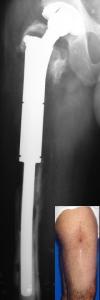

17 yaşında erkek hastada ateşli silah yaralanması sonucu sağ femurda oluşan 14 cm kemik defekti ve 5 cm kısalığın, önce eksternal fiksatör i...